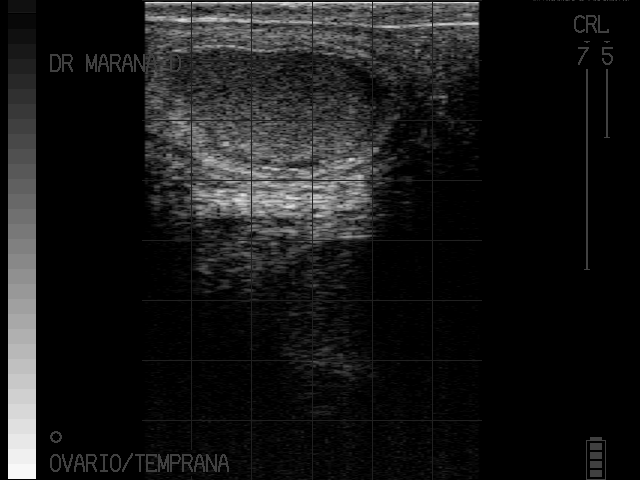

Abceso utero

Piometra severa

imagenes cortesia:

MVZ MsC David Maraña Peña Especialista en Reproducción Bovina